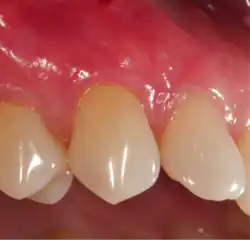

A free gingival graft is a dental procedure where a small layer of tissue is removed from the palate of the patient's mouth and then relocated to the site of gum recession. It is sutured (stitched) into place and will serve to protect the exposed root as living tissue. The donor site will heal over a period of time without damage. This procedure is often used to increase the thickness of very thin gum tissue.

A subepithelial connective tissue graft takes tissue from under healthy gum tissue in the palate, which may be placed at the area of gum recession. This procedure has the advantage of excellent predictability of root coverage,[19] as well as decreased pain at the palatal donor site compared to the free gingival graft. The subepithelial connective tissue graft is a common procedure for covering exposed roots.